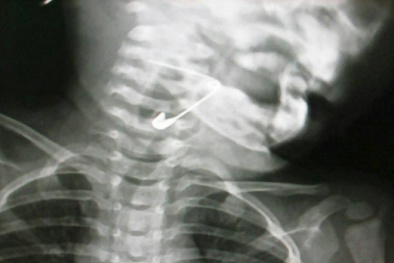

Bé trai bị ngưng tim sau khi ăn bánh mì kẹp xúc xích